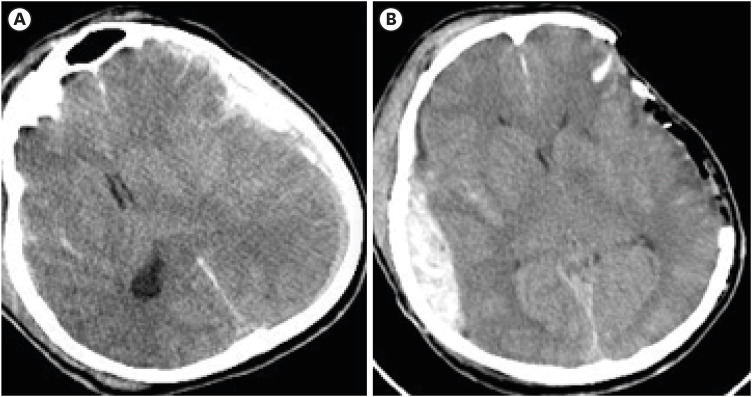

Objective: This randomized controlled trial (RCT) aimed to compare the short-, mid-, and long-term outcomes in patients with malignant intracranial hypertension undergoing either decompressive craniectomy (DC) or hinge craniotomy (HC).

Methods: In this prospective RCT, 38 patients diagnosed with malignant intracranial hypertension due to ischemic infarction, traumatic brain injury, or non-lesional spontaneous intracerebral hemorrhage, who required cranial decompression, were randomly allocated to the DC and HC groups.

Results: The need for reoperation, particularly cranioplasty, in the DC group was significantly different from that in the HC group. The percentage of brain expansion was higher in the DC group versus the HC group; however, the difference was not significant. There was no significant intergroup difference in the functional outcome according to the modified Rankin Scale or the Glasgow Outcome Scale. Additionally, no significant intergroup differences were observed in the rates of in-hospital complications.

Conclusion: The HC and DC groups did not significantly differ in the rate of hospital complications such as infection, need for reoperation owing to the lack of intracranial pressure control, wound healing problems, or bone infection. Our results suggest that by performing HC, the probability of the need for major surgery (cranioplasty) is reduced, thereby removing financial burden from the patient and the health system.